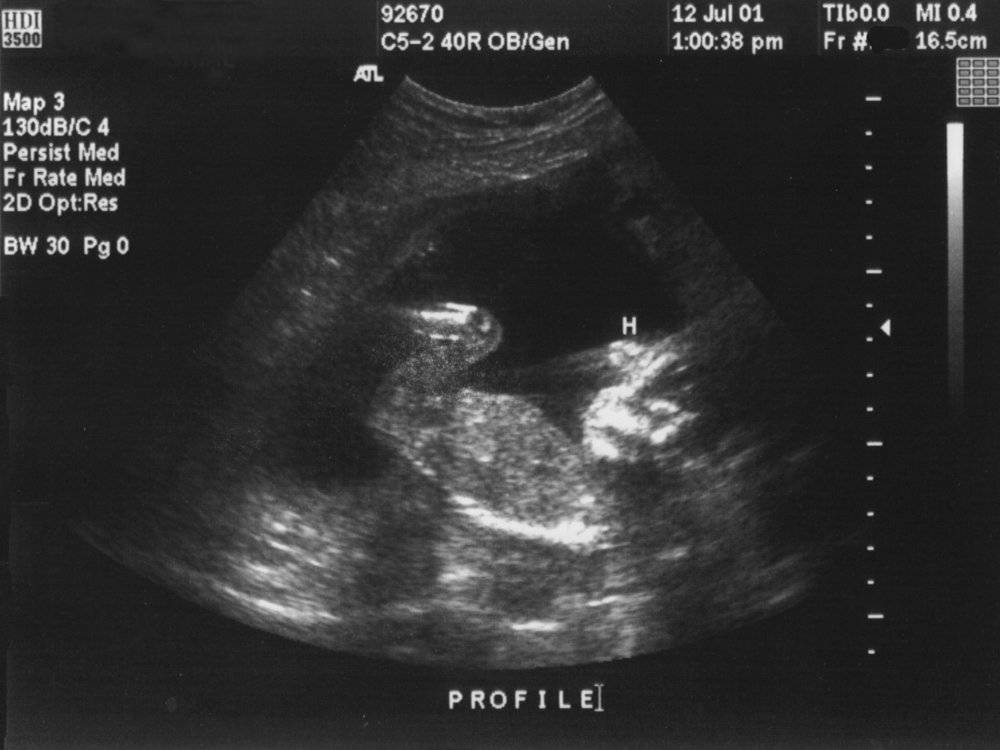

УЗИ на 14 неделе беременности

Но ведь ультразвуковое исследование не только и не столько проводится для определения пола ребеночка и его размеров. УЗИ на 14 неделе беременности – один из очень информативных методов оценить степень развития плода и соответствие этого развития норме. Тем более, что установить такое соответствие уже достаточно просто: плод на этом сроке имеет размеры, достаточные для четкой визуализации всех его структур.

Главные параметры, которые оцениваются при помощи УЗИ на 14 неделе беременности – это копчико-теменной размер малыша (длина, рост плода от макушки до копчика); бипариетальный размер (поперечный размер головки плода); окружность головки и окружность живота. Также УЗИ на 14 неделе беременности позволяет измерить длину бедра ребеночка, и одновременно – соотношение двух бедренных костей для исключения пороков развития.

Дополнительно специалист проводит оценку развития длинных костей плода (локтевых, лучевых, плечевых, малоберцовых и большеберцовых), стоп и кистей ручек. А с ними – и оценку развития внутренних органов: сердца, желудка, почек, кишечника, мочевого пузыря, мозга.

14-я неделя беременности — время для планового визита к врачу и сдачи анализов мочи и крови. Если необходимо, гинеколог назначает УЗИ. Ультразвуковое исследование на этом сроке дает возможность оценить развитие будущего ребенка, определить, как работают его внутренние органы (мозг, сердце, желудок, почки, кишечник, мочевой пузырь). Пол малыша установить еще сложно. Но с помощью аппаратуры, работающей с 3D-форматом, это возможно.

Плод имеет достаточно большие размеры, поэтому уже можно не только измерить его «рост» от макушки до копчика, но и установить длину бедра и соотношение бедренных костей: это нужно для того, чтобы исключить наличие пороков развития.

Также УЗИ проводится с целью выявить хромосомные аномалии на сроке 14 недель беременности. Но будущая мама должна иметь в виду, что при негативных показателях результаты ультразвукового исследования не могут считаться заключительным диагнозом — для его подтверждения необходимы дополнительные анализы и обследования. Например, при подозрении на синдром Дауна в период 13 – 14 недель беременности проводится биопсия хориона (ворсинчатой оболочки плодного яйца).